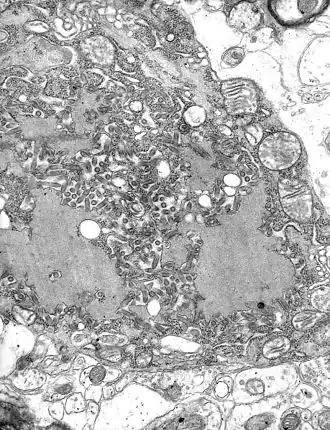

Une fois fixé, le virus est internalisé dans la cellule par des vésicules endosomiques. La fusion des membranes virales et cellulaires libère les nucléocapsides dans le cytoplasme. La transcription du génome viral se fait à l'aide de la polymérase L et de la phosphoprotéine P.

Les molécules d'ARN néosynthétisées sont encapsidées et la maturation des nouveaux virus commence. Toutes ces étapes s'effectuent dans le cytoplasme. L'accumulation des nouveaux virus dans le cytoplasme forme des amas visibles en microscopie optique : les corps de Négri. Les particules virales sont ensuite libérées à la membrane cytoplasmique.